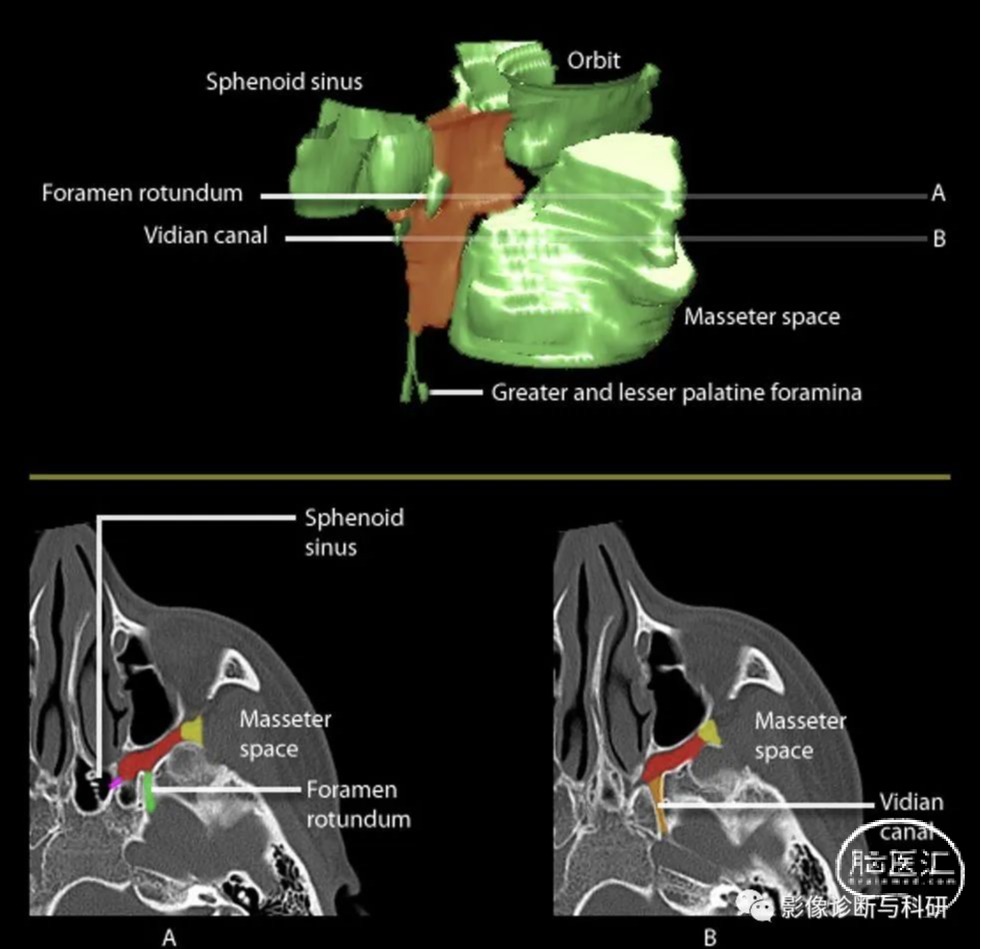

1区(下颌空间)--位于上颌窦后外侧壁与颞肌和翼状肌之间的空间。上颌窦的后外侧壁与颞肌和翼状肌之间的空间。2区(上翼间空间)--包括翼外肌的上端头、V 3和翼外肌之间的区域。 第4区(颞肌空间)--颞肌外侧的空间。(主要由脂肪组成)。- 第5区(咽鼓管区域)--包括咽鼓管、张肌和腭上提肌。(翻译可能有出入!)

4、翼腭窝

翼腭窝经8个通道与周围相交通